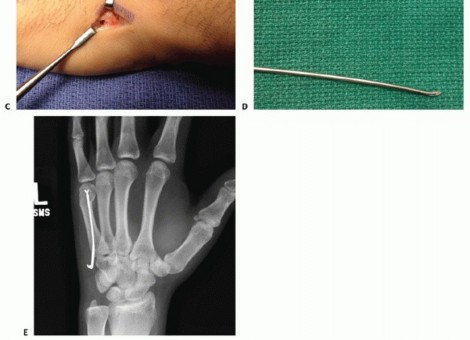

Percutaneous and Intramedullary Techniques

For transverse or short oblique fractures of the metacarpal neck and shaft, particularly in the fifth metacarpal, percutaneous or minimally invasive intramedullary techniques offer excellent stability while sparing the dorsal soft-tissue envelope. The procedure begins with a closed reduction utilizing the Jahss maneuver: the MCP and PIP joints are flexed to 90 degrees, relaxing the intrinsic muscles and tightening the collateral ligaments, allowing the proximal phalanx to be used as a lever to push the metacarpal head dorsally, correcting the apex-dorsal angulation.

Once reduced, fixation can be achieved via crossed Kirschner wires or retrograde intramedullary pinning (the "bouquet" technique). However, the modern gold standard for minimally invasive fixation is the retrograde intramedullary headless compression screw. A small stab incision is made over the dorsal aspect of the flexed MCP joint. The entry portal is meticulously established in the articular "safe zone" of the metacarpal head—specifically the dorsal-ulnar or dorsal-radial collateral recess, strictly avoiding the central weight-bearing articular cartilage.

A guidewire is advanced down the medullary canal across the fracture site under fluoroscopic guidance. After confirming perfect rotational alignment and length, the canal is sequentially broached or drilled, and an appropriately sized headless compression screw is buried beneath the articular cartilage. This technique provides robust, load-sharing stability that allows for immediate, unrestricted active range of motion, vastly reducing the incidence of postoperative stiffness compared to traditional K-wire constructs.